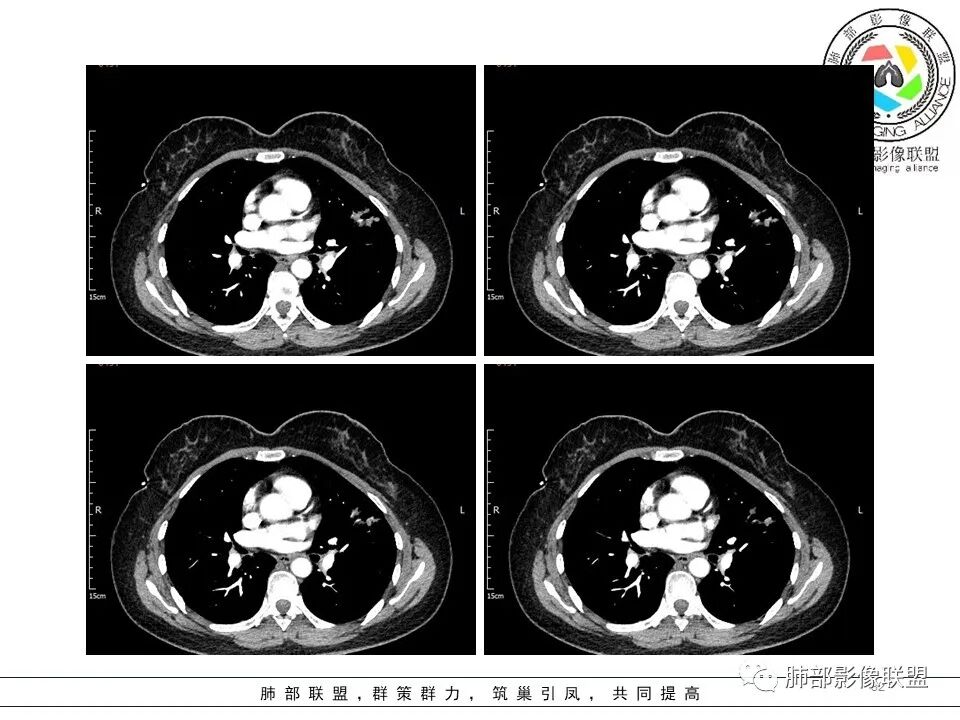

3.病灶实性密度区强化明显,这有助于我们区分一些其他类似病灶,如结核灶等!

结合临床,应当高度怀疑浸润性肺腺癌!